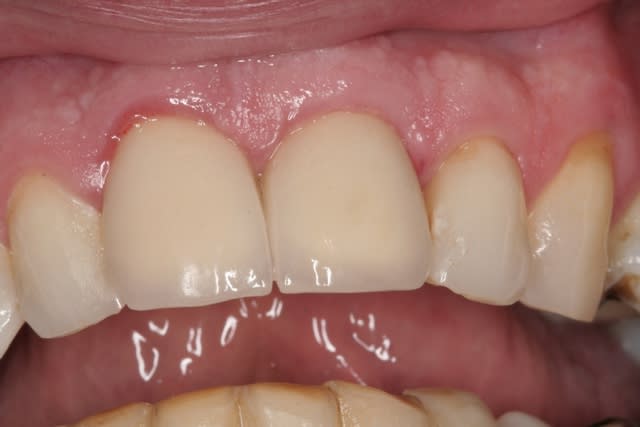

çà manque un peu de cas en ce moment...alors en voilà un ptit au passage...

11 avec résorption interne

EII avec MCI sur du dentium (4.5/14) comblement du gap vestibulaire avec du kasios tcp (très constant dans les résultats...et très économique)

pas de photos de chir par contre...j'ai du les effacer par erreur...grrrr...

la prothèse d'usage a été réalisée par ma petite associée...mais j'étais là pour superviser et faire quelques photos...;-)